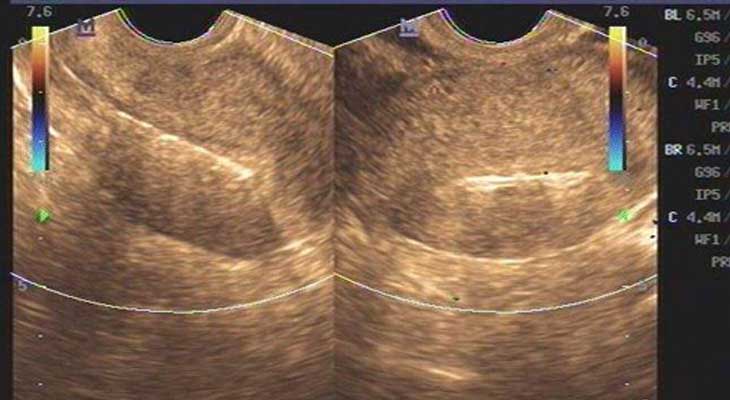

窦卵泡计数(AFC简介)

AFC是窦卵泡计数的缩写,是指利用B超彩超等等对卵巢的卵泡数目、大小来进行其的计数手段之一,而窦卵泡常说的是女性卵巢内直径在2-10mm的小卵泡,而通过窦卵泡计数也能够非常好的反应出卵巢储存功能等等。

窦卵泡计数监测

通过阴超的方式见监测,而不管是哪一种方式,它们最终都是窦卵泡计数监测通常都是用起来起到观察基础卵泡的作用,而对于窦卵泡计数监测的方式非常的多,但是监测的使用方法也是有好有坏的。

1、2D阴超检查

在2D阴超检查的时候必须进行进行对膀胱排空后方可进行,而常常需要在两个平面进行连续的扫查,找出成像较佳平面,并进行超声调整后再做最为准确的卵泡液与卵巢间质间的对比度。

2、3D阴超检查

相对于2D阴超来说3D阴超下过要好一点,3D阴超是同时利用3个垂直平面存储和分析产生体积,通过多平面交叉进行窦卵泡计数检查,将效果发挥到最佳,在较好切面直接进行最佳图像参数和最大采集角,将成像图片质量提升到最高